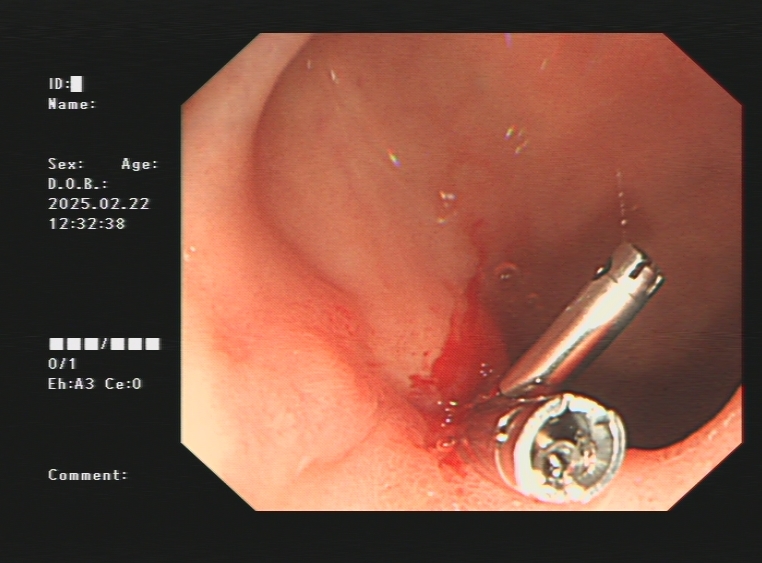

1.上消化道出血常见原因:消化性溃疡(胃溃疡、十二指肠溃疡)、食管炎、急性糜烂出血性胃炎、上消化道肿瘤(食管癌、胃癌)、剧烈呕吐造成的食管贲门黏膜撕裂伤、肝硬化引起的食管胃底静脉曲张。以下是一些常见的上消化道出血内镜图片:

急性胃黏膜病变出血、十二指肠球部溃疡出血及镜下止血夹止血

肝硬化引起的食管及胃底重度静脉曲张镜下止血

食管贲门黏膜撕裂出血